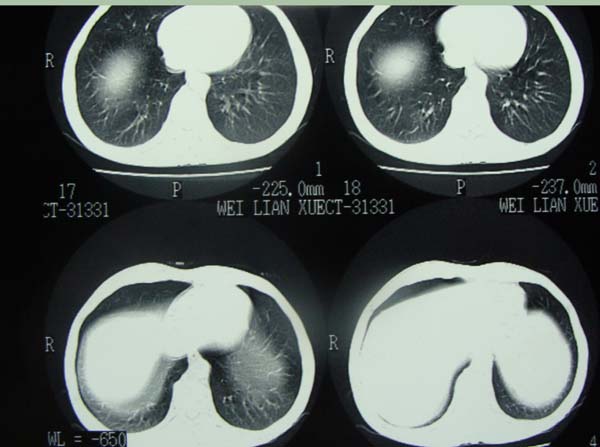

以下是引用宝天曼在2009-6-21 22:48:00的发言:[br]首先考虑肺tb

以下是引用泪洒红尘在2009-6-21 21:55:00的发言:[br]考虑结核合并感染。